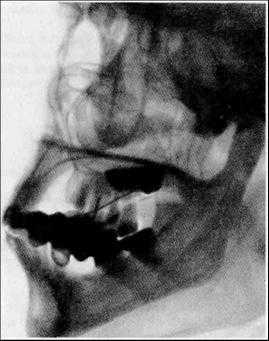

3. Внеротовые (экстраоральные) рентгенограммы.

Внеротовые рентгенограммы дают возможность оценить состояние отделов верхней и нижней челюстей, височно-нижнечелюстных суставов, лицевых костей, не получающих отображения или видимых лишь частично на внутриротовых снимках.

Ввиду того что изображение зубов и окружающих их образований получается менее структурным, внеротовые снимки используют для их оценки лишь в тех случаях, когда выполнить внутриротовые рентгенограммы невозможно (повышенный рвотный рефлекс, тризм и т.п.).

Рентгенографию тела и ветви нижней челюсти в боковой проекции проводят на дентальном рентгенодиагностическом аппарате.